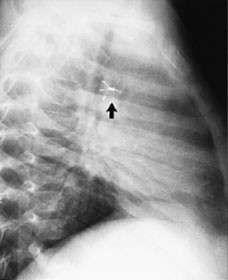

Av de 100 første pasientene har 90 fått sin ductus komplett lukket, noen av dem først etter repetisjon av lukking med den samme eller en annen teknikk (fig 4). Lukkingsraten ved de tre metoder er summert i tabell 2. Den er ikke signifikant høyere i noen av gruppene, men man ser en tendens til at de som ble behandlet med spiral, har et bedre resultat enn paraplygruppen. Etter reintervensjonene er gruppene statistisk sett like. Dog må anføres at de siste 20 initiale prosedyrene med spiral har ført til komplett lukking hos alle, og at alle ductuser som er forsøkt lukket med Amplatzer-propp er tette. Men dette er åpenbart for små tall til å fanges opp med statistiske metoder.